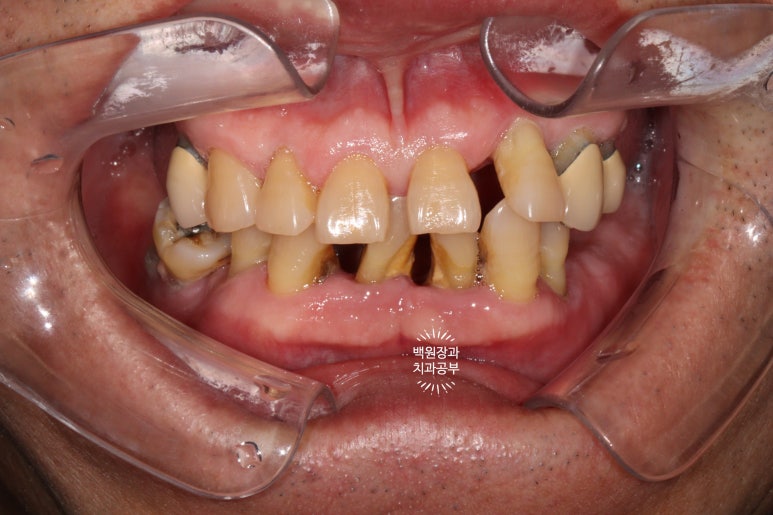

정면에서 찍어본 구강 내 사진 소견입니다.

다수의 치은연상치석, 치은연하치석이 침착되어 있고, 만성치주염으로 인해 치아가 제 위치를 상실하여,

치아의 병적이동 (pathologic migration)을 하고 있는 중이었죠.

풍치가 심해서 만성치주염을 오래 앓으신 분들은 치아 사이가 벌어져 심미적으로 불리한 모습을 많이 보이십니다.

게다가, 어금니들도 씹는 면끼리 물리지 못해서 이제 식사도 어려우신 상황이었어요.